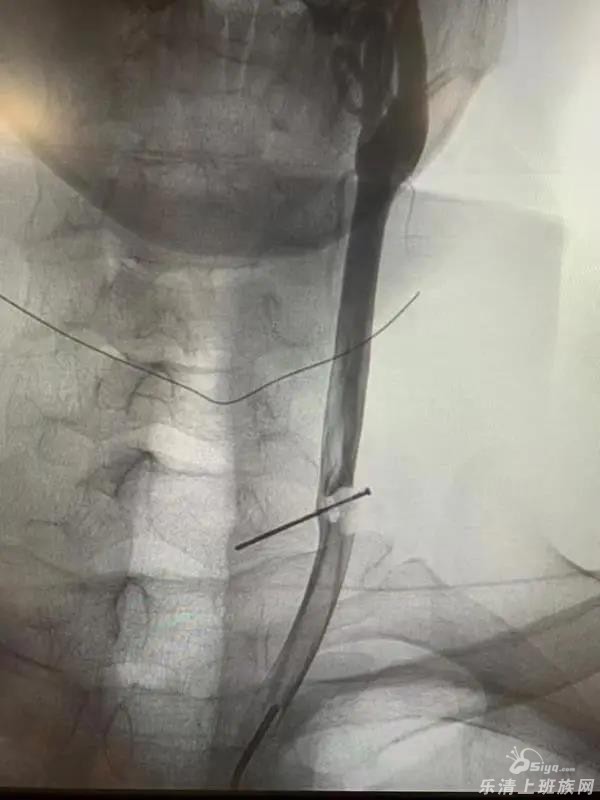

不管懂不懂医术,大多人都知道颈动脉“伤不起”,电视剧里颈动脉被割破后血喷如注的场景也让人心生恐惧。然而要说在现实中,有人的颈动脉被铁钉洞穿,并且“潜伏”人体里10余年,当事人还好好活着,这你信不信? ...